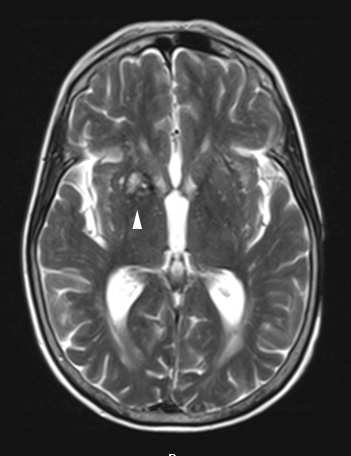

Case 31 History ---- The patient is a 72 year old woman with pancreatic adenocarcinoma, status post distal pancreatectomy, recurrent and metastatic to liver and bilateral lungs with extension into the lesser curvature of the stomach. Routine MRI examination as part of her metastatic workup showed a cavernous angioma. ---- 31A This T2-weighted MRI scan shows a “popcorn” pattern diagnostic of cavernous angioma.